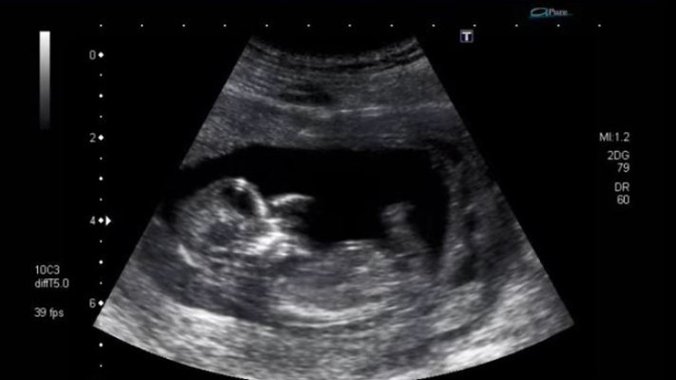

Osećaj kada buduća mama, bez obzira na to koji put očekuje dete, oseti da se beba koju nosi mrda neprocenjiv je. Ovaj snimak pokazuje kako se to bebe pomeraju dok su u stomaku.

Ovo je snimak koji pokazuje kako to izgleda "iznutra", a milioni su ga pogledali neverovatnom brzinom, pa je on postao i viralan.